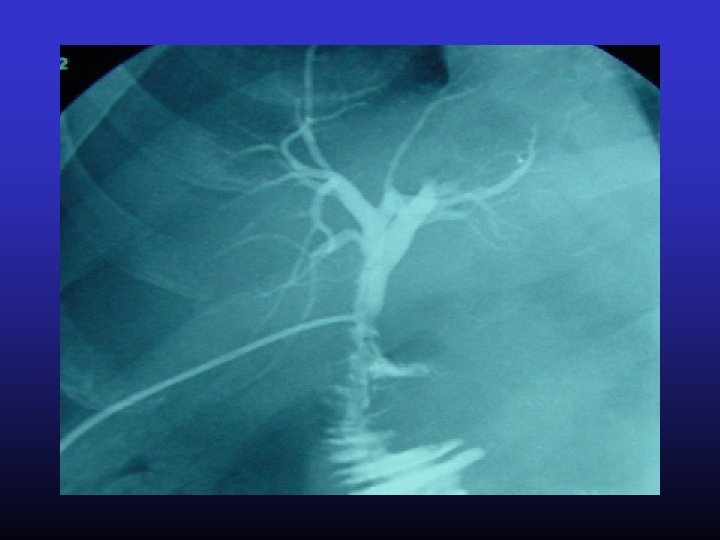

PTC

Diagnostiek galsteenlijden • Echo – Percutaan – Endoscopisch – Intraoperatief • • • Open • laparoscopisch CT MRCP HIDA (etc) Cholangiografie – – oraal ERCP PTC Intraoperatief